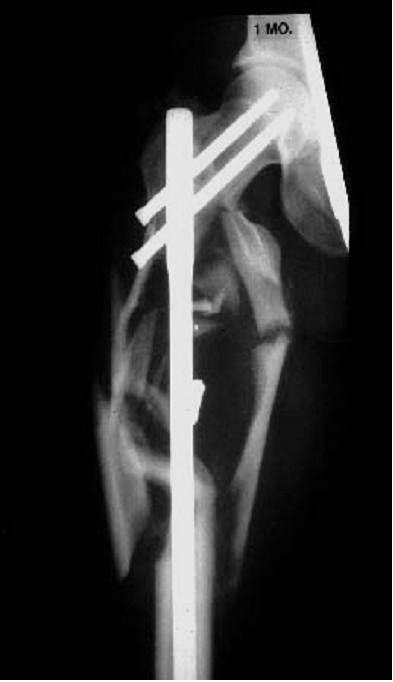

Коллеги,На Ваш взгляд, сросся ли этот перелом? Это к вопросу о "идеальной анатомической фиксации".Джолдас

Этот перелом ещё не сросся, я думаю Вы это тоже видите. Этот перелом находиться в процессе сращения - есть калюс на снимке.

Судя по всему, перелом полностью консолидирован. Вас можно поздравить.